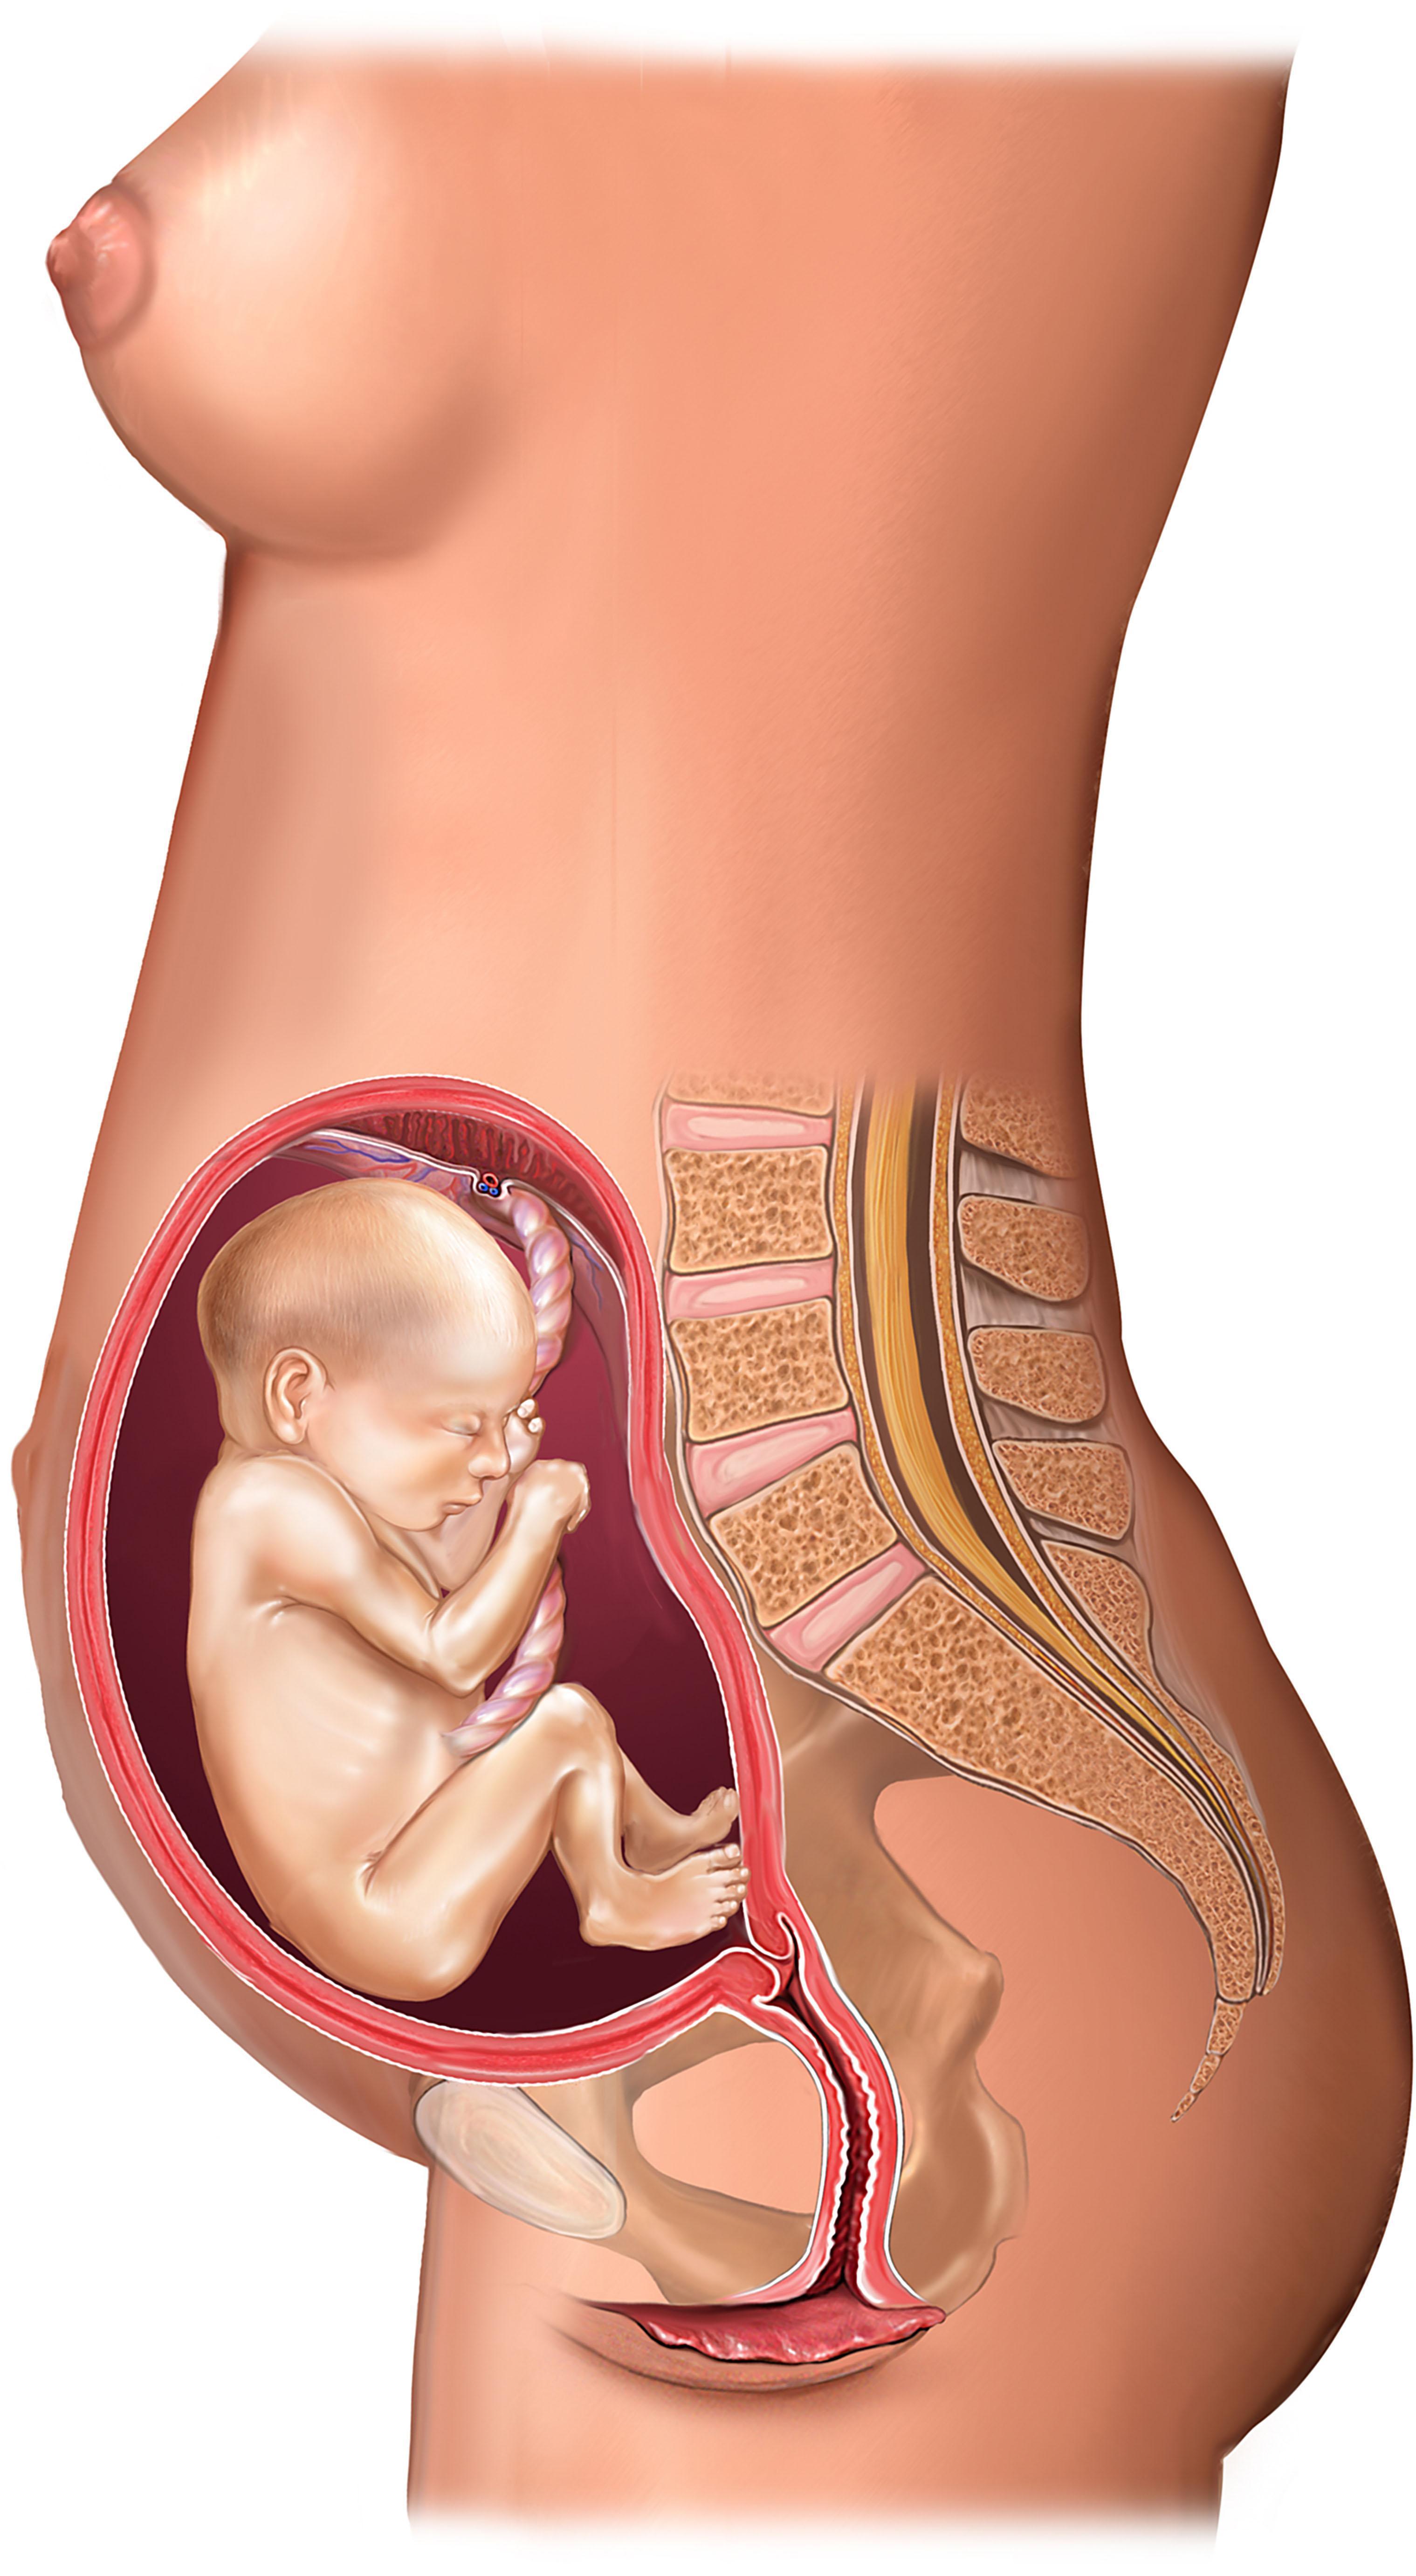

16-17 недель беременности: развитие малыша

Раздел: Житейские мотивы